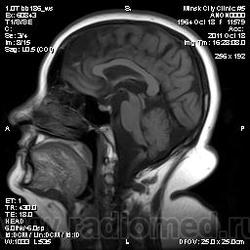

Деформация ствола и продолговатого мозга

Женщина с жалобами на головокружение, нарушение координации движений, двоение в глазах. Жалобы беспокоят около 6 лет. В анамнензе гипертония (АД до 200), сейчас (после наступления менопаузы) - гипотоник 100/60... МР-ангиография - позволяет "резать" только веллизиев круг (такие ограниченные возможности системы)...

по поводу жалоб - добивался как мог - говорят появились около 6 лет назад, медленно прогрессировали. С чем либо конкретным появление жалоб не связывает... А деформация по моему за счет значительно изогнутой основной артерии с диаметром около 8 мм на всем протяжении. Дополнительной косточки я не вижу...

нейроваскулярный конфликт между основной артерией и стволом .

Ну, круто изогнулась базиллярис! Но причина не врожденная, скорее всего всего гипертония и атеросклероз.

А мне кажется долихоэктазия и патологическая извитость основной артерии.

А двоится скорее всего за счет компрессии глазодвигательных нервов, больше правого.

Сдавление продолговатого мозга извитой базилярной артерией. Аневризмы вроде бы не видно... А какие еще могут быть варианты?